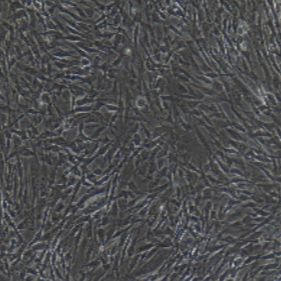

Ⅱ型肺泡细胞(ATⅡ)又称颗粒肺泡细胞,散在分布于ATⅠ肺泡细胞(ATⅠ)之间及其相邻的肺泡间隔结合处。其体积较小,呈立方形,表面稍突向肺泡腔。细胞核大而圆,胞质染色较浅淡,胞质中常见空泡。数量较ATⅠ多,ATⅡ占肺泡上皮细胞总数的14%到16%,但仅覆盖5℅的肺泡表面。ATⅡ体积比ATⅠ小很多,人约为900um3 .在细胞游离面有较多的短微绒毛,尤其在细胞边缘部更多。细胞表面有 MPA凝集素,对α-半乳糖残基有特异性反应。相邻细胞以紧密连接或中间连接相连,胞质内有较多的线粒体和粗面内质网,还有多泡体、溶酶体和板层体[1]。ATⅡ是肺泡上皮细胞的“干细胞”,它的功能多样:能增殖成新的ATⅡ,还可以分化为其他上细胞如ATⅠ;合成和分泌表面活性物质的功能;肺水转运功能;强大的免疫功能。这些功能与以下疾病有密不可分的关系。

| 形态特性 | 多角形细胞 | 生长特性 | 贴壁生长 |

1) 细胞来源于人正常肺组织。

2) 细胞鉴定:肺表面活性蛋白 A(SP-A)或肺表面活性蛋白 C(SP-C)免疫荧光染色为阳性。

3) 经鉴定细胞纯度高于 90%。

4) 不含有 HIV-1、 HBV、HCV、支原体、细菌、酵母和真菌。

5) 细胞生长方式:上皮样,多角形细胞,贴壁培养。